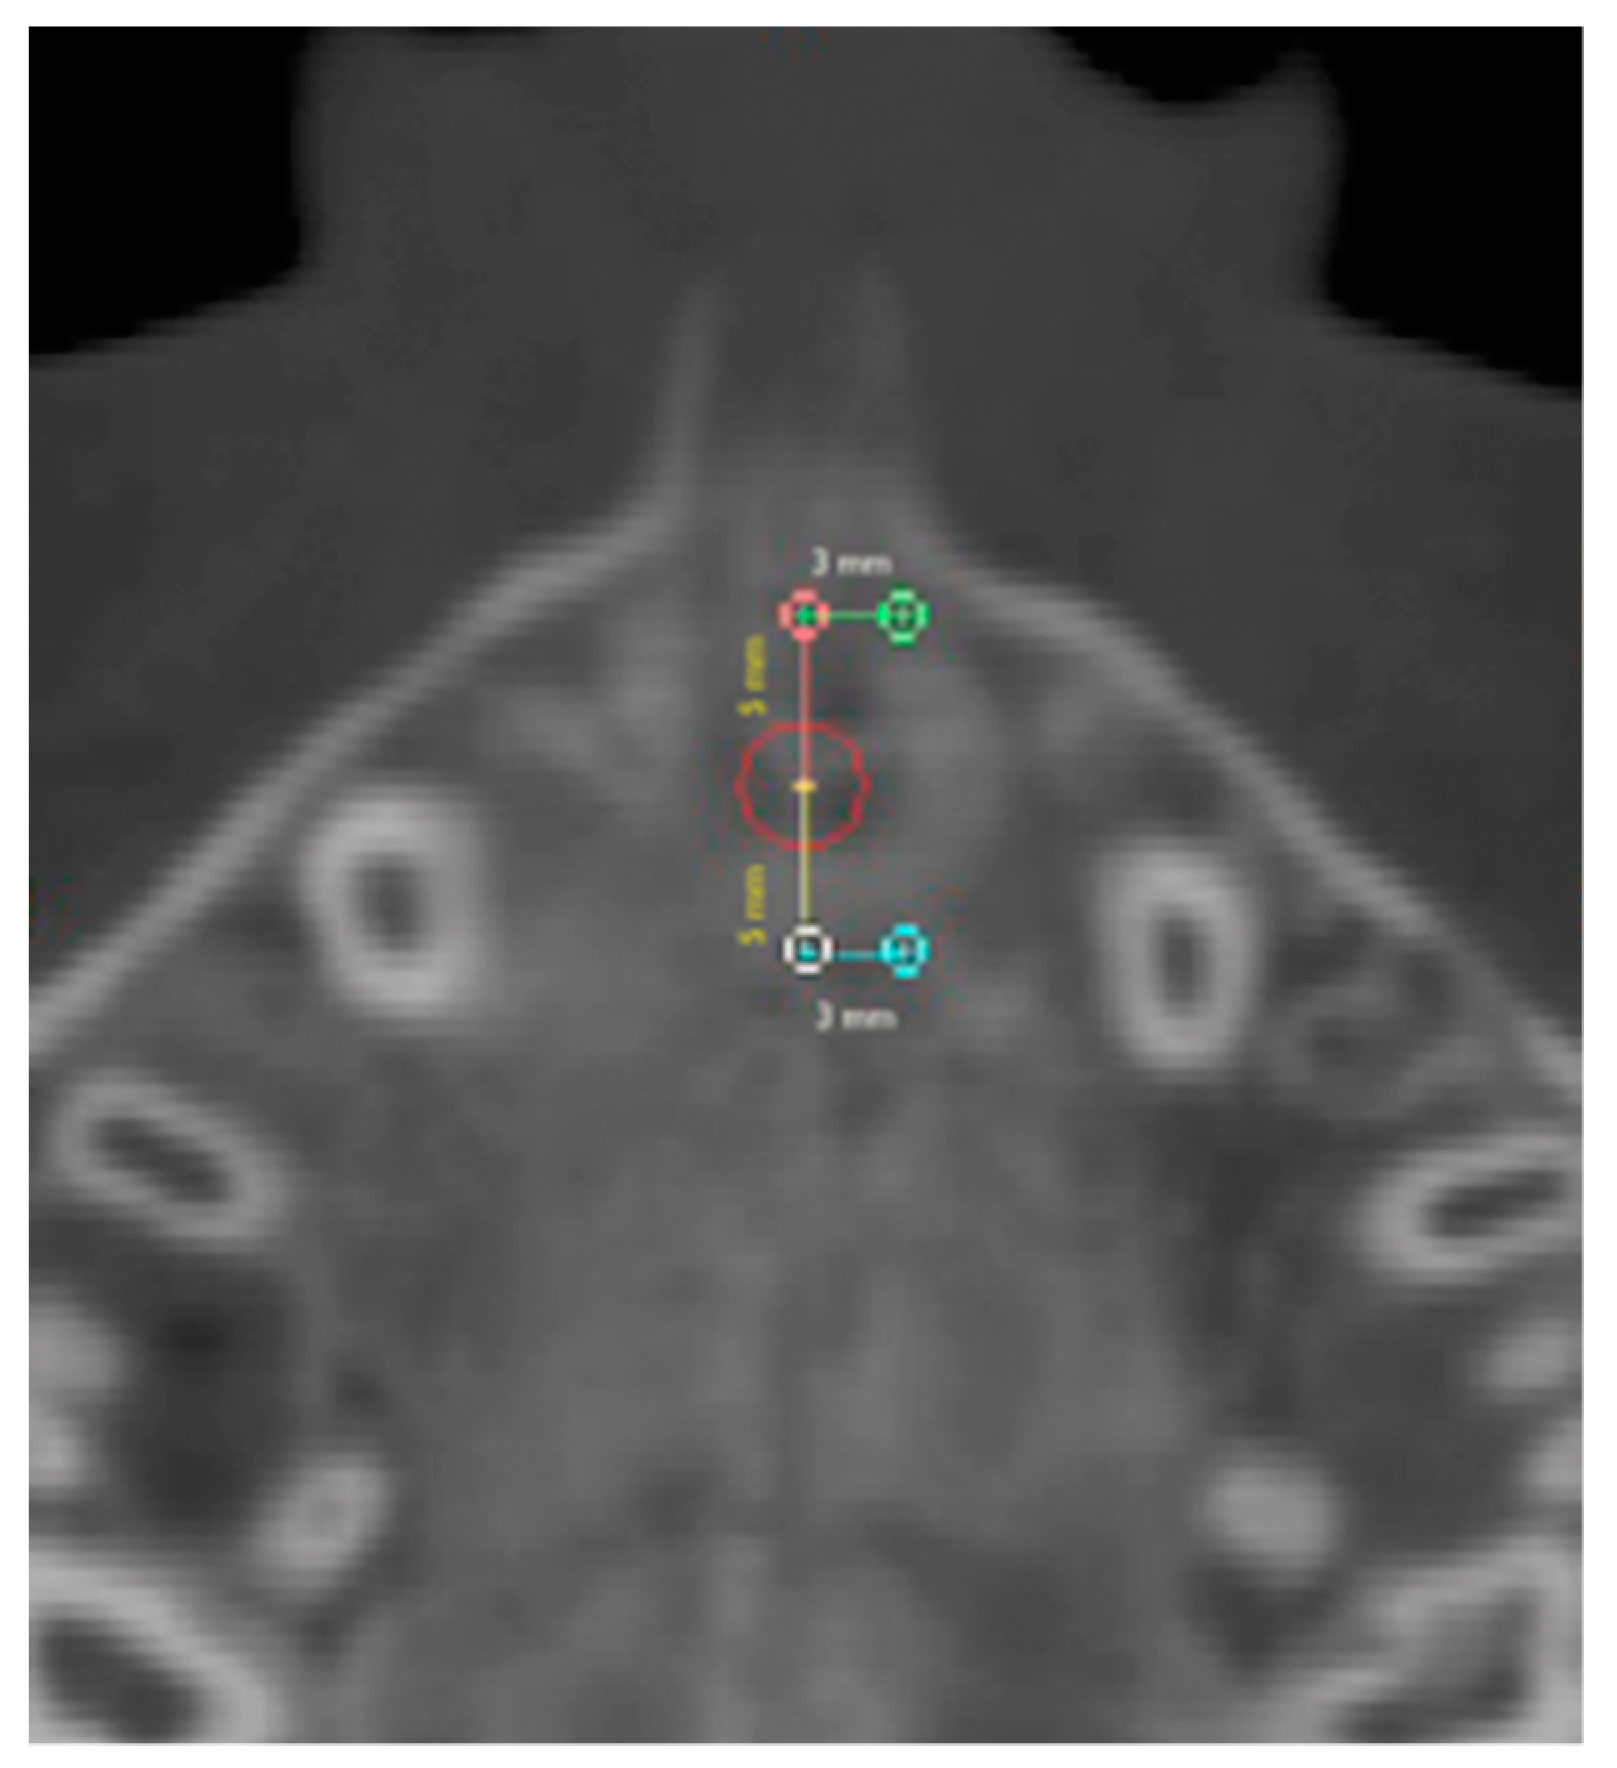

2.1. Round-Shaped ROIs

2.2. Rectangular-Shaped ROIs